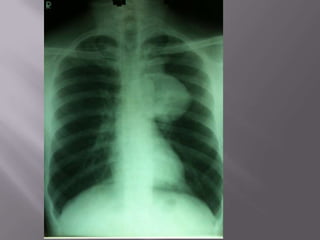

 Thymoma presenting on a chest radiograph

obtained before orthopaedic surgery in an

otherwise asymptomatic elderly female patient.

There is a large anterior mediastinal mass (A) with

coarse calcification visible on (B) the lateral view

and (C) contrast-enhanced CT.